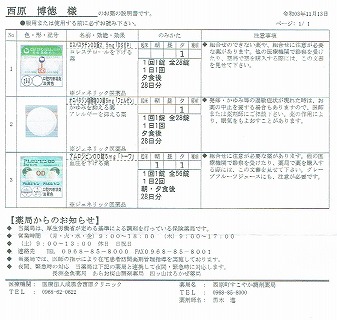

2021.11.13より 西原クリニック 0968-62-0622

2025.1.31より 江崎耳鼻咽喉科 0968-62-5533

2025.1.31(金) 脳ドックによる副鼻腔炎の疑いから左目に涙が出る障害の件で受診

レントゲンによる検査で蓄膿症とまでは行っていない。左の鼻はかなり詰まっている。

採血によりアレルギー検査(大きな8項目)

レボセチリジン塩酸塩錠5mg「武田テバ」 モンテルカスト錠10mg「トーワ」